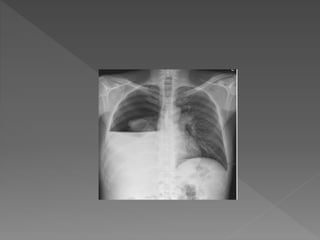

Chest xray

 An anteroposterior chestxray should be done in all

children with suspected pleural effusion. Atleast 300ml of

fluid should be present to detect effusion clinically and

radiographically in AP view.

 Lateral decubitus CXR with affected side inferior allows

recognition of smaller volumes of fluid.

 Xray features- Obliteration of costophrenic and cardiophrenic

angles

 homogenous opacity of affected hemithorax with mediastinal

shift to contralateral side

Chest xray  Ananteroposterior chestxray should be done in all children with suspected pleural effusion. Atleast 300ml of fluid should be present to detect effusion clinically and radiographically in AP view.  Lateral decubitus CXR with affected side inferior allows recognition of smaller volumes of fluid.  Xray features- Obliteration of costophrenic and cardiophrenic angles  homogenous opacity of affected hemithorax with mediastinal shift to contralateral side